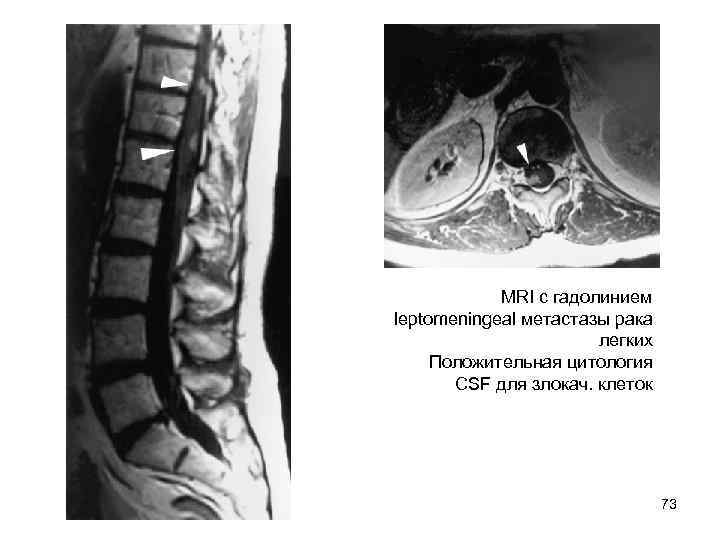

MRI с гадолинием leptomeningeal метастазы рака легких Положительная цитология CSF для злокач. клеток 73